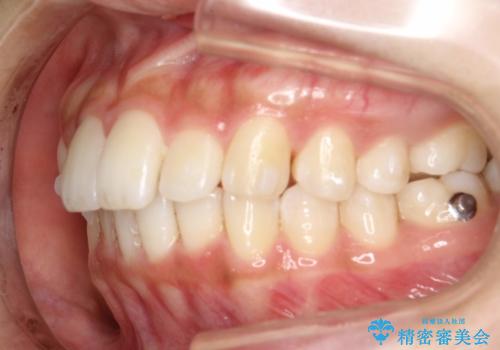

Invisalign インビザラインによる軽度なガタつきの改善

- 奥歯の位置関係はそこまで大きくいじらず、前歯群のみでガタつきの改善を計画しました

奥歯の位置関係に改善の余地はありますが、機能的に問題のない cusp to fossa の関係で咬めているため、前歯のガタつきを前歯のみで改善するというシンプルな計画で、短期間で治療を終了させました。